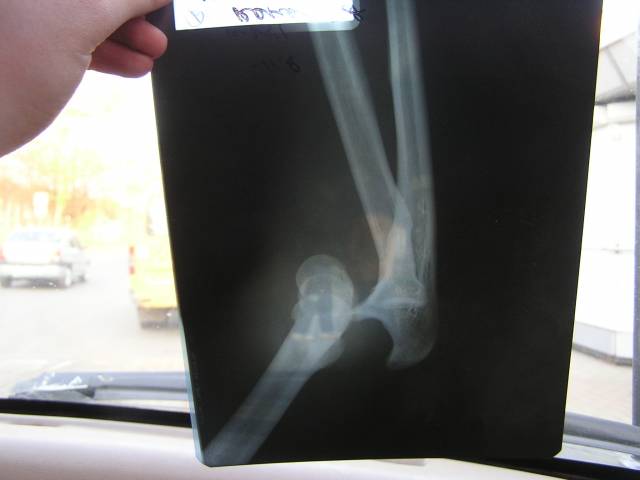

креш

вывих левого предплечья.

в чулково на корнях расколбасило. вот

валер это локоть или что?

это локоть

это не просто вывих, это в конец раз[мат]ченый локоть, парень, мне тебя жаль, выздоравливай.